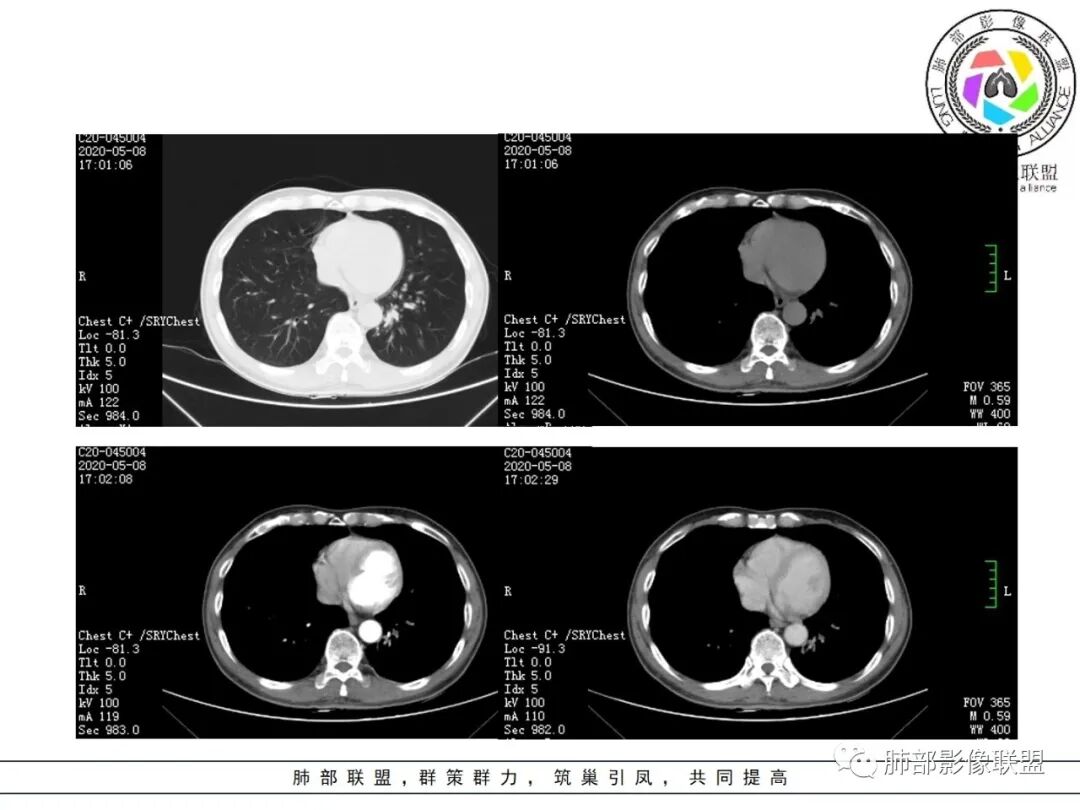

影像所见:

结节伴分叶。

斑片影,考虑阻塞性炎症。

支气管壁厚,支气管腔内高密度影填充。

2.关于支气管:上述病灶辖区外侧段支气管截断,环壁结节,远端阻塞性肺炎,是肺癌的重要征象。

3.关于胸膜增厚:本例未见明显的胸膜凹陷及牵拉。病灶较小价值收缩力不强,同时因鳞癌的破坏力强,也抵消了肿块本身的收缩力。

5.关于阻塞性肺炎:同一部位反复发生的感染,治疗效果不佳或反复发生,应仔细搜寻相关气道异常,警惕肿瘤导致阻塞性肺炎的可能。